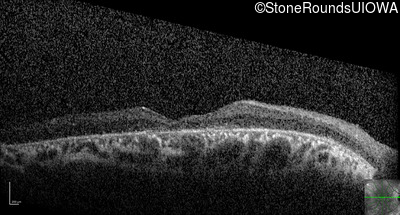

Optical Coherence Tomography - Right - 20/63 +1

Exemplar / OCT Stack

OCT Stack